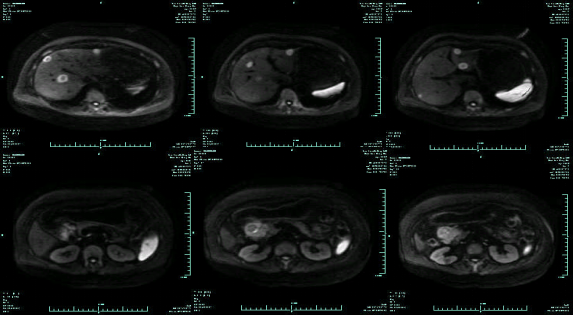

• MR示:

CT-T

CT-H1

MR-H1

影像学检查结果评估:cPD。